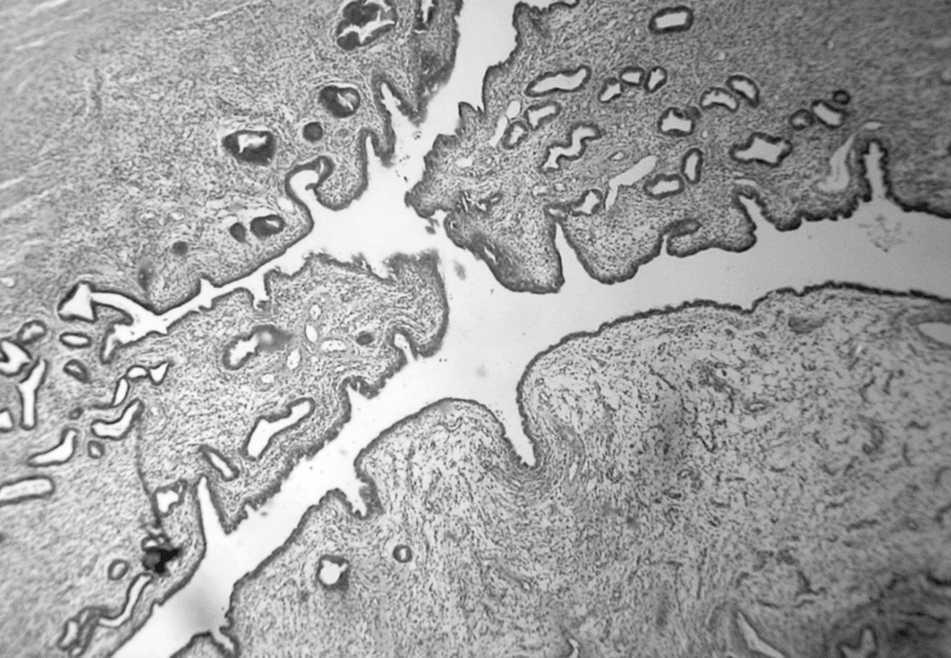

El paciente evolucionó bien, y se le dio de alta según protocolo de cirugía ambulatoria. Se envió el material a anatomía patológica cuyo informe reveló desarrollo de endometrio y miometrio en un saco herniario (fig. 1).

Fig. 1. Macrofotografía de la trompa de Falopio.